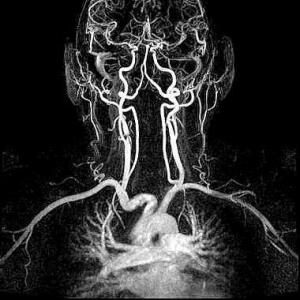

Die Kernspintomographie liefert detailgenaue Schnittbildaufnahmen des menschlichen Körpers ohne Röntgenstrahlen – und das sogar von Blutgefäßen. Bei der MRT werden Sie in einem starken Magnetfeld untersucht. Ähnlich wie bei einem Radio werden UKW-Wellen verwendet. Um dünne Schichtaufnahmen zu erzeugen, benötigen wir zusätzlich schwach wechselnde Magnetfelder, wodurch ein lautes Klopfgeräusch entsteht. Die Signale werden dann von einem sehr leistungsfähigen Computersystem zu Schichtaufnahmen in verschiedenen Ebenen umgewandelt. Die Untersuchung dauert je nach Fragestellung 7 bis 35 Minuten. Während der Messzeit sollten Sie ruhig und entspannt liegen, denn jede Bewegung verursacht Bildstörungen und verlängert die Prozedur.